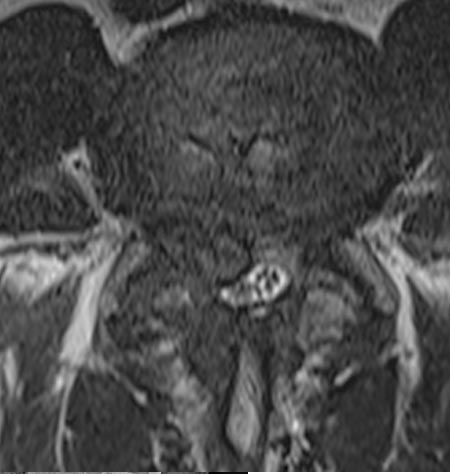

50 year old man presenting with left biceps and triceps weakness with numbness in his hand.

C6 corpectomy with complete resolution of the weakness and numbness.